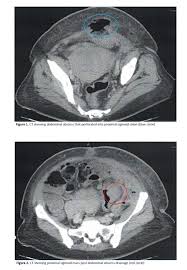

Can Colon Cancer Be Mistaken For Diverticulitis / Difference In Clinical Features Between Right And Left Sided Acute Colonic Diverticulitis Scientific Reports : Diverticulitis involves common digestive tract growths called diverticula.. (diverticulitis, appendicitis, colon cancer, chronic inflammatory disease of the intestine) should be sought for any. If left untreated, diverticulitis can lead to a collection of pus outside the colon wall or a generalized infection in the lining of the abdominal cavity, a condition known as peritonitis. The diagnosis of cancer was made within 6 months from the date. Colon cancer however is caused by small lumps that progress into cancerous tumors. Because the symptoms of ibs, colon cancer, and some other gastrointestinal.

In the retrospective part of the study, 27 patients were diagnosed with diverticulitis and 31 were diagnosed with colon cancer. It does not appear that diverticulitis and cancer are heavily linked, as the former is a very common condition that is generally easily treated. Patients who present with acute diverticulitis may have significant abdominal pain and fever, which may be confused with inflammatory bowel disease or peptic ulcer disease. Diverticular disease and the risk of colon cancer. I thought i may have ovarian cancer from all the symptoms, which are painful left abdominal pain, lower backache which is constant, pain in groin and down left leg, fever and then chills, very fatigued to the point of dragging myself through the day, constipation, frequent and urgent need to urinate and now nauseus as well. When colonic obstruction is present, colon cancer is more likely than diverticulitis. Colon polyps are growths on the inner lining of the colon, and diverticulitis happens when a diverticulum ruptures and becomes infected. The most frequent issues with the bowel or colon, affect the colon's ability to work properly. However, people with diverticulitis may be at higher risk of developing colon polyps. Colon polyps do not cause diverticulitis. Screening for colon cancer can detect and remove precancerous polyps before they have the chance to develop into cancer. I had 10 or 12 inches of colon removed. Went for a ct before a surgery could be scheduled for scar tissue in my abdomen.

Diverticulitis is a condition set off by infection or rupture of diverticula,. Sure, a ct scan can be consistent with diverticulitis, but many other conditions can precisely mimic this ct scan appearance. I was diagnosed with diverticulitis with a severe infection; It does not appear that diverticulitis and cancer are heavily linked, as the former is a very common condition that is generally easily treated. Symptoms of diverticulitis and colon cancer may include abdominal pain. The most frequent issues with the bowel or colon, affect the colon's ability to work properly. August 8, 2009 at 12:09 pm. Yes diverticulosis is benign, has distinct appearance from ca on ct for a trained radiologist will read as accurate as reading finger prints, some times in between diverticula the wall may be thickened, may have mucosal overgrowth will mimic a early cancer, then colonoscopy indicated, at 39 cancer is not common but age is not exception for ca, ask again for referral. Diverticulitis involves common digestive tract growths called diverticula. Screening for colon cancer can detect and remove precancerous polyps before they have the chance to develop into cancer. Patients who present with acute diverticulitis may have significant abdominal pain and fever, which may be confused with inflammatory bowel disease or peptic ulcer disease. When colonic obstruction is present, colon cancer is more likely than diverticulitis. Although at first diverticulitis and colon cancer may present similar symptoms, they are two very different conditions.

August 8, 2009 at 12:09 pm. During diverticulitis, diverticula become infected or inflamed. But when they do show up, the symptoms can mimic those of crohn's disease. Recent textbooks claim that can colon cancer be mistaken for diverticulitis coexist in a high percentage of cases. Screening for colon cancer can detect and remove precancerous polyps before they have the chance to develop into cancer. When colonic obstruction is present, colon cancer is more likely than diverticulitis. This can lead to symptoms that are similar to colon cancer symptoms, such as severe abdominal pain, changes in bowel habits, and rectal bleeding. About 1% of colon polyps will become colon cancer. But can it actually cause. Usually a ct scan is needed to diagnose an abscess, and treatment usually requires a hospital stay, antibiotics applied through a vein and possibly drainage. Colon polyps and diverticulitis are two different digestive tract conditions. If left untreated, diverticulitis can lead to a collection of pus outside the colon wall or a generalized infection in the lining of the abdominal cavity, a condition known as peritonitis. Patients who present with acute diverticulitis may have significant abdominal pain and fever, which may be confused with inflammatory bowel disease or peptic ulcer disease.